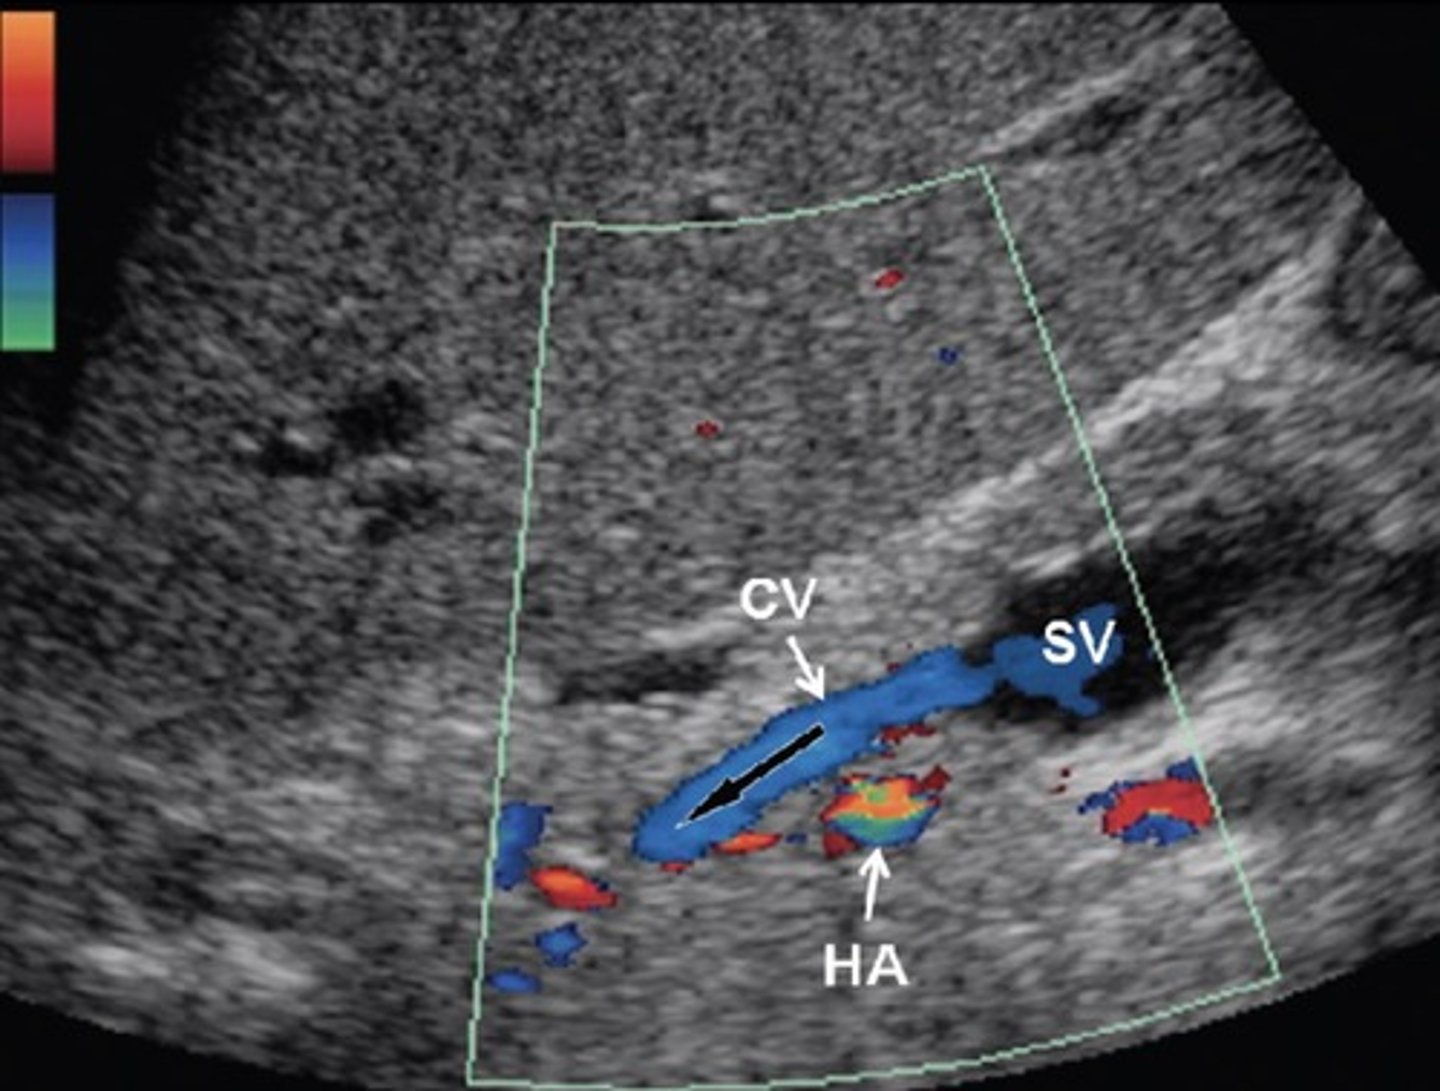

Pre-Hepatic/Inflow Vessels

Portal Vein

Hepatic Artery

Hepatic Artery Doppler Waveform

Hepatopetal

Low resistant monophasic pan-diastolic forward flow

Hepatic Buffer Response

When PV flow increases, HA flow decreases (post-prandial)

Splenic Vein Doppler Waveform

Hepatopetal flow

Continuous monophasic with slight respiratory variation